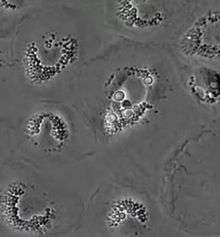

Vomocytosis is the cellular process by which live organisms that have previously been engulfed by a white blood cell are expelled without being destroyed. Vomocytosis was first reported in 2006[1][2] by two groups, working simultaneously in the UK and the USA, based on time-lapse microscopy footage characterising the interaction between macrophages and the human fungal pathogen Cryptococcus neoformans. Subsequently, this process has also been seen with other fungal pathogens such as Candida albicans[3] and Candida krusei.[4] It has also been speculated[5] that the process may be related to the expulsion of bacterial pathogens such as Mycobacterium marinum[6] from host cells. Vomocytosis has been observed in phagocytic cells from mice, humans and birds,[7] as well as being directly observed in zebrafish[8] and indirectly detected (via flow cytometry) in mice.[9]

The mechanism of vomocytosis remains unclear although it is known to be influenced by inflammatory signals[10] and rearrangements of the actin cytoskeleton[11] within the host cell. Different morphologies[12] of vomocytosis have been documented and it is possible that the underlying cellular mechanism may vary between them.